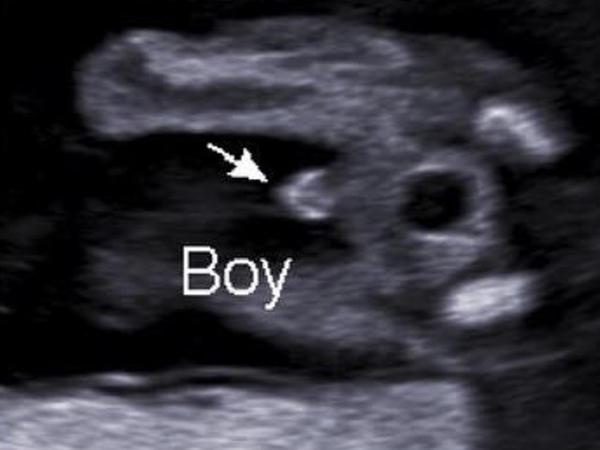

@bsvet chlapeček

@sabinakarlova to je pidník,podle mě 🙂